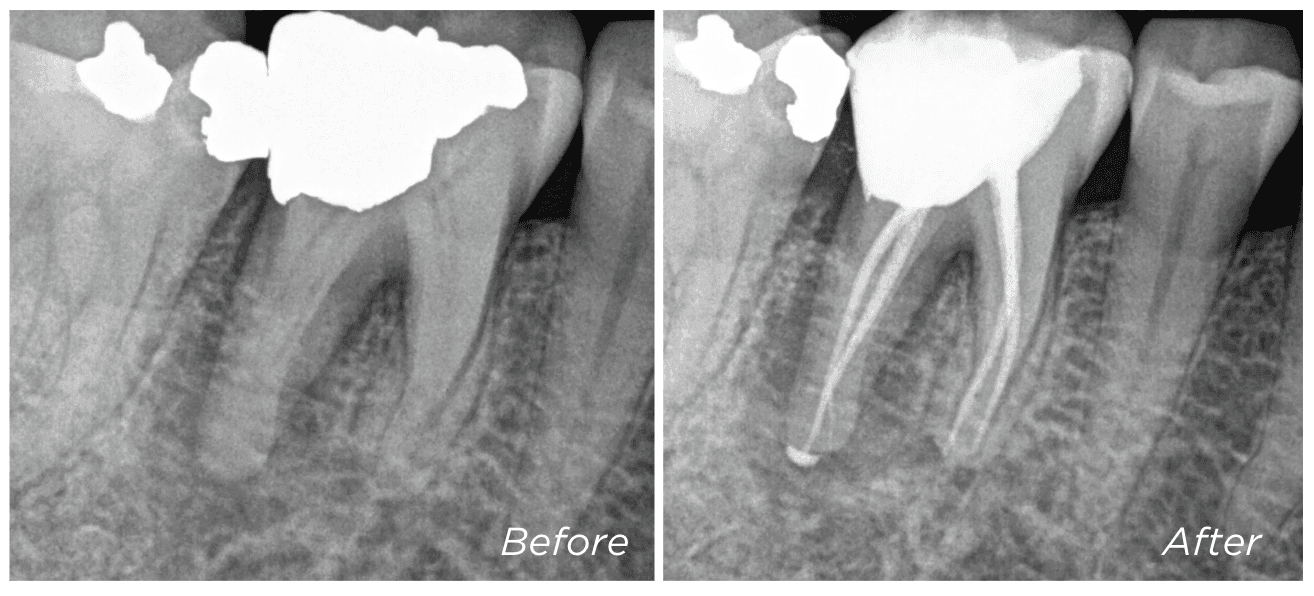

Some teeth are referred to us as “unrestorable” — meaning the decay has extended too deep to reliably place a new filling or crown. But in many cases, we’re able to save these teeth using a technique called deep margin elevation (DME).

This involves carefully removing the old filling and placing a new restoration deeper into the tooth — using special techniques to ensure it is secure and well sealed.

We won’t know if DME is possible until the old filling has been removed and we can assess how much healthy tooth remains. If we’re able to place a well-sealed restoration, the tooth may still be suitable for root canal treatment and long-term restoration.

If DME isn’t an option, surgical crown lengthening may help expose more of the tooth — this is explained in the next section.

Dr Kreena Patel is often referred teeth that others consider unsalvageable — and she will always explore every option to help preserve your natural tooth wherever possible